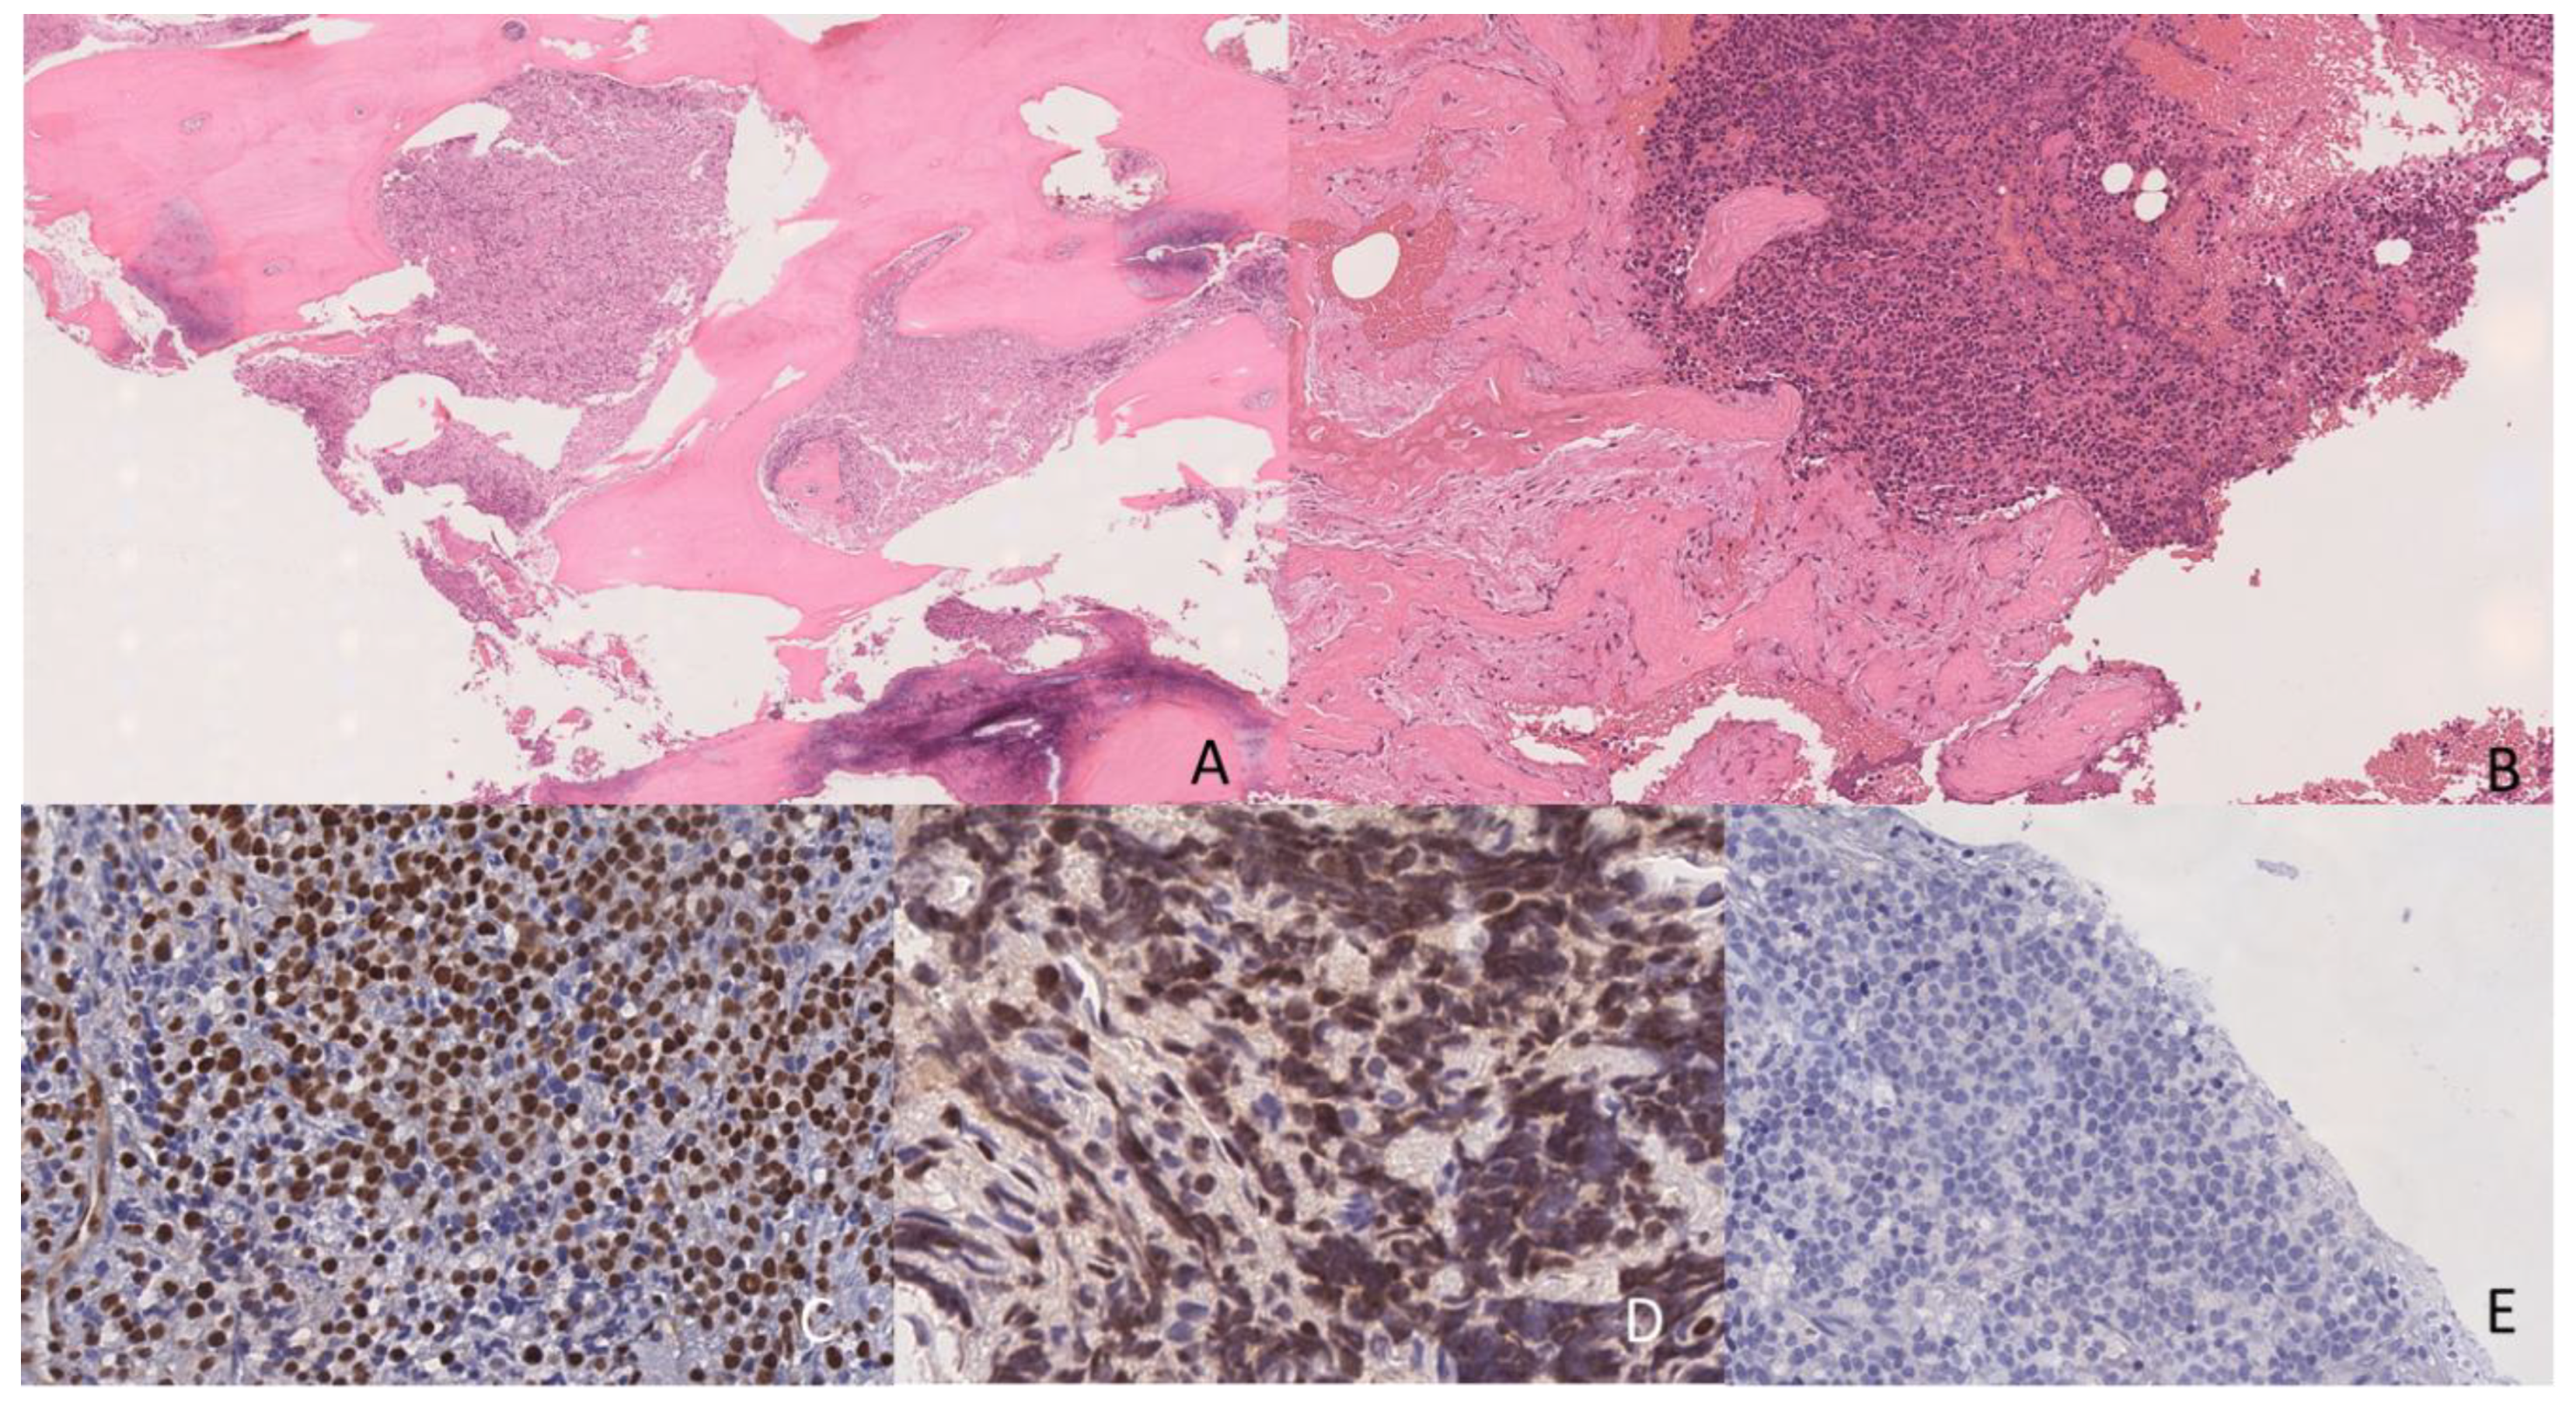

- Chisholm, K.M.; Smith, J.; Heerema-McKenney, A.E.; Choi, J.K.; Ries, R.E.; Hirsch, B.A.; Raimondi, S.C.; Wang, Y.C.; Dang, A.; Alonzo, T.A.; et al. Pathologic, cytogenetic, and molecular features of acute myeloid leukemia with megakaryocytic differentiation: A report from the Children's Oncology Group. Pediatr Blood Cancer 2023, 70, e30251. [CrossRef]

- Brouwer, N.; Matarraz, S.; Nierkens, S.; Hofmans, M.; Novakova, M.; da Costa, E.S.; Fernandez, P.; Bras, A.E.; de Mello, F.V.; Mejstrikova, E.; et al. Immunophenotypic Analysis of Acute Megakaryoblastic Leukemia: A EuroFlow Study. Cancers (Basel) 2022, 14. [CrossRef]